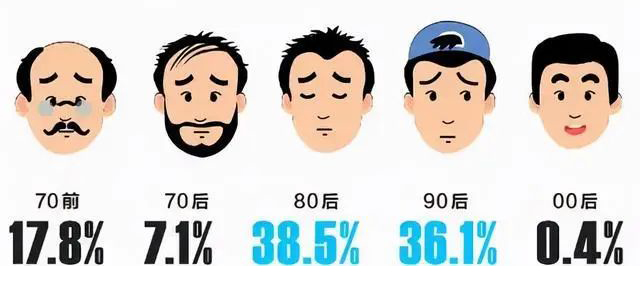

当代年轻人苦头发已久,《中国人头皮健康白皮书》数据显示,我国脱发人数已超2.5亿人(男性约1.63亿,女性约0.88亿,相当于每4位男性中有1人脱发,每8位女性中有1人脱发。与此同时,30岁前脱发的比例高达84%,较上